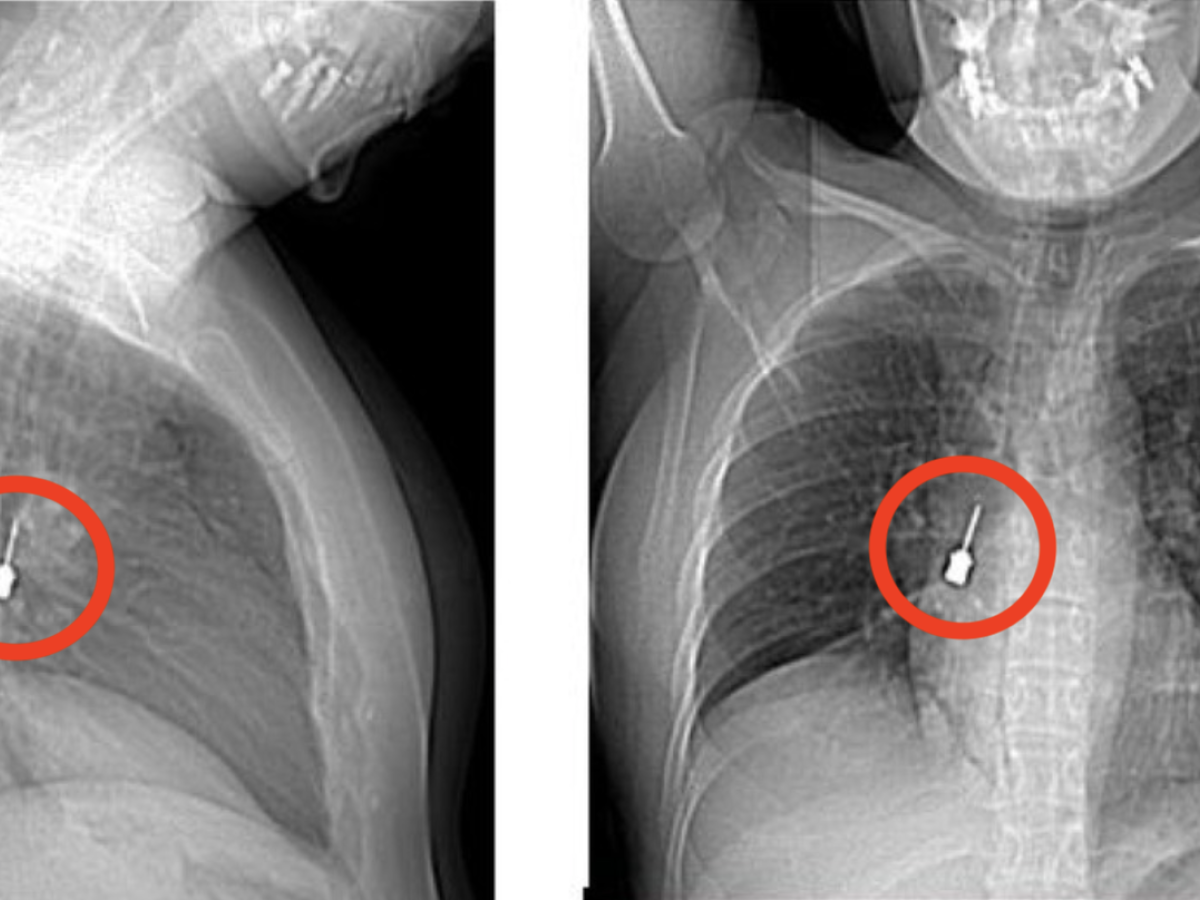

Una giovane donna si è presentata al Pronto Soccorso del Grande Ospedale Metropolitano (G.O.M.) di Reggio Calabria dopo giorni di tosse persistente e dolore intenso al petto. I medici, dopo aver visionato una Tomografia Computerizzata (un esame diagnostico di imaging medico che permette di ottenere immagini dettagliate dell’interno del corpo utilizzando raggi X e un computer), hanno fatto una scoperta sorprendente, un cacciavite odontoiatrico accidentalmente inalato era rimasto incastrato nel bronco lobare inferiore del polmone destro, provocando anche un pneumomediastino, ossia la presenza di aria nello spazio tra i due polmoni. La paziente, preoccupata dai sintomi e dalla persistenza della tosse, aveva eseguito la TC per chiarire l’origine del malessere, portando così alla luce un caso potenzialmente molto pericoloso. 🔗 Leggi su Ilgiornale.it

Tosse e dolore al petto, i medici scoprono un cacciavite odontoiatrico incastrato nel bronco di una donna - Un cacciavite odontoiatrico inalato accidentalmente e rimasto incastrato in un bronco polmonare. msn.com